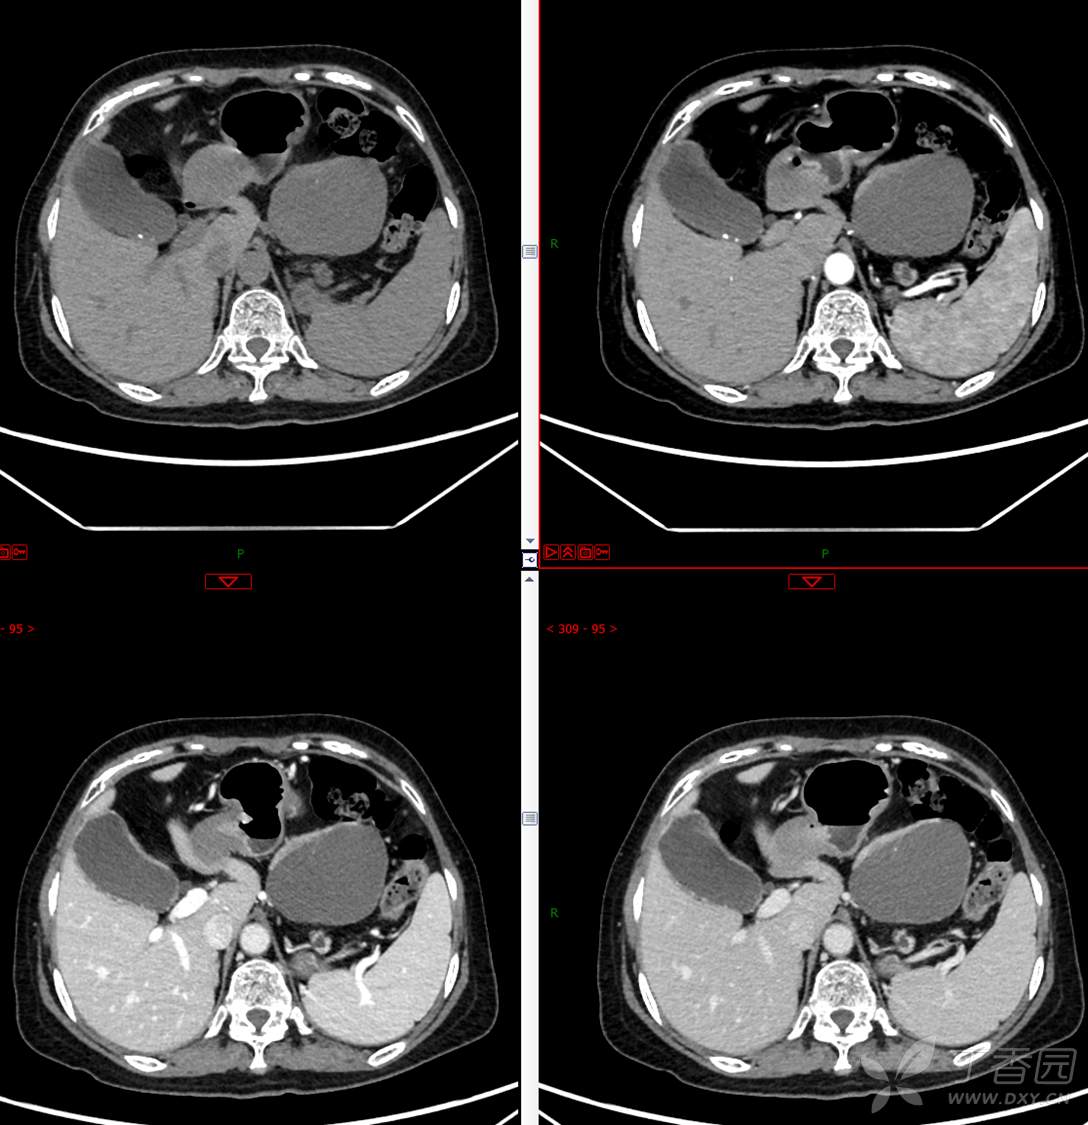

主 诉:发现胰腺占位性病变3月

现病史:患者3月前就诊于**市人民医院行腹部增强CT发现胰尾占位性病变,无腹痛、腹胀,无恶心呕吐,无黄疸,无呕血黑便,无胸闷憋气,无寒战高热,未行特殊治疗